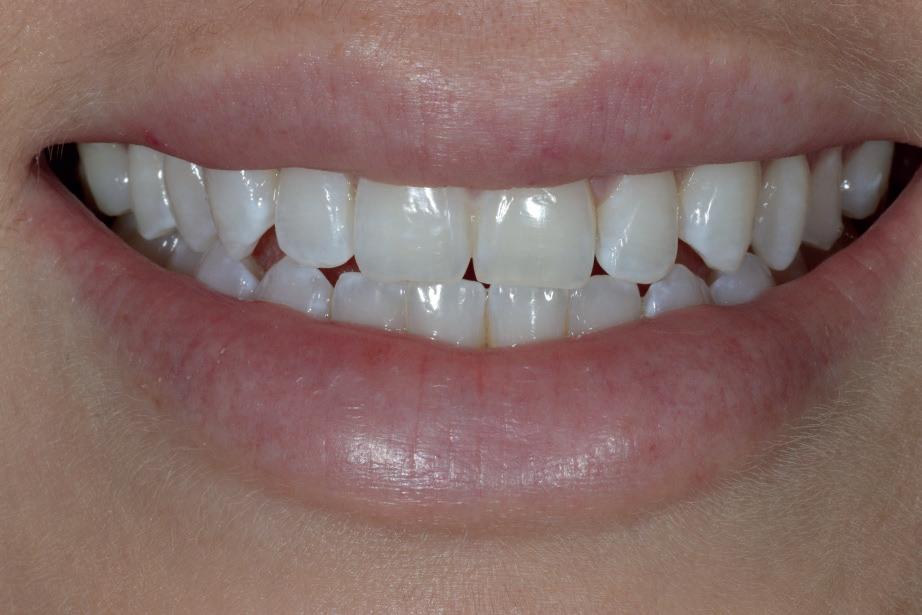

Marketing and branding yourself using social media platforms is essential as a selfemployed individual. Breaking that fear and anxiety of showcasing and promoting your before-and-after work, and highlighting patient testimonials on social media is not only important to demonstrate your skillset as a young dentist but also to boost your reputation and recognition for welcoming new patients. Having been fortunately selected as a finalist for multiple awards in the past including this year’s Dental Awards, it has not only boosted my esteem and confidence as a young dentist, but has encouraged me to keep steering this journey forward for the benefit of my patients’ healthcare and my own ability to provide excellent dentistry. Plus, receiving a shiny plaque to put on the wall for patients to see provides a confidence boost for them, as well as myself.

I personally use Instagram for my content. I was always hesitant to post images of my work in fear of being judged by other dentists, but eventually overcame this and told myself to have confidence in the quality of my work and just do it. That mindset has worked in my favour since. Sharing before-and-after cases (with patient consent), posting educational videos about common procedures, and fun moments behind the scenes to make your practice feel welcoming speaks for itself. Be sure to engage with your audience by answering questions, responding to comments and showing that you care.